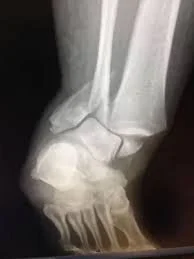

An ankle fracture is a break in one or more of the bones that form the ankle joint, most commonly the tibia (shinbone), fibula (outer leg bone), and occasionally the talus, which connects the leg to the foot. Ankle fractures are common lower extremity injuries and may occur after a twisting injury, fall, sports-related trauma, or high-energy accidents such as motor vehicle collisions.

An ankle fracture occurs when excessive force causes one or more bones of the ankle joint to break. The severity of an ankle fracture can range from a simple, stable injury to a complex fracture involving multiple bones and joint instability.

Ankle fractures are classified based on which bones are involved and whether the ankle joint remains stable. Common types include:

More complex fractures may be associated with ligament injury, joint displacement, or instability, which often requires surgical treatment to restore proper alignment.

Diagnosis begins with a thorough history and physical examination, followed by X-ray imaging to evaluate fracture location, alignment, and joint involvement. In certain cases, CT scans may be used to better assess complex fractures and assist with surgical planning.